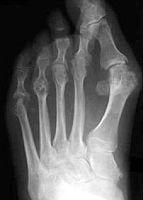

Ce este piciorul reumatoid?

Deformarea piciorului din poliartrita reumatoida (PAR).

- Atingerea ante-piciorului este frecventa (la circa 70 - 90% din pacientii cu poliartrita reumatoida), determinand impotenta functionala dureroasa si deformatii foarte greu tolerate;

- Se observa aparitia "monturilor" si a deformatiilor (grifelor) digitale extrem de rapid, uneori intr-un interval de circa 6 luni. Aspectul este cel al "monturilor" foarte evoluate, insa este vorba despre o alta entitate, piciorul reumatoid;

- Sunt atinse articulatiile metatarso - falangiene laterale, atat la nivelul cartilajului cat si al componentelor stabilizatoare (capsula, placa plantara,ligamente), formatiunile teno-sinoviale ale muschilor lungi si ale spatiilor inter si sub-metatarsiene, precum si anumiti muschi intrinseci ai piciorului. Se produce progresiv o fragilizare a tuturor acestor structuri, majoritatea contribuind la sustinerea piciorului si fiind responsabile de aspectul clinic al piciorului reumatoid. De fapt, PAR nu face decat sa precipite problemele arhitecturale care ar fi aparut inevitabil in cadrul unui picior “de tip static”;

- Atingerile metatarso-falangiene laterale sunt frecvente si precoce, dar nu evolueaza catre anchiloza, spre deosebire de articulatiile halucelui (metatarso - falangiana sau inter-falangiana);

Deformatiile antepiciorului sunt de diferite tipuri:

- picior triunghiular;

- deviatie fibulara;

- deviatie tibiala;

- degete in “foc de iarba” (deviate in toate directiile).